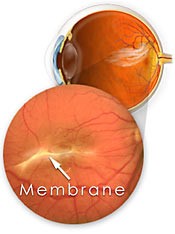

Ocorre a membrana epiretiniana quando na superfície da retina há proliferação de células sobre a mácula formando uma membrana. Esta membrana tende a contrair, levando à distorção da anatomia macular e da visão.

Tomografia de retina mostrando uma membrana na superfície da retina

O diagnóstico é feito através do mapeamento de retina (fundo de olho) e confirmado com tomografia da retina (OCT).